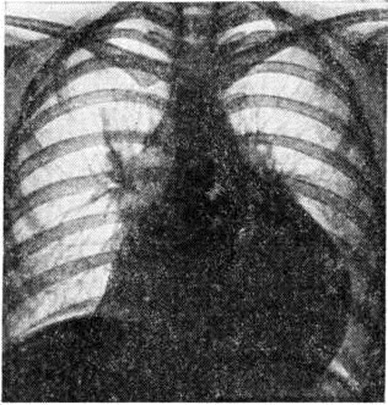

При больших количествах выпота в полости перикарда диагностическое значение приобретают признаки сдавления органов средостения (затруднённое глотание, охриплость голоса) и тампонады сердца (приступы слабости с холодным липким потом, снижение АД, частый малый пульс и другие). Кроме резкого расширения границ сердца, отмечается снижение громкости его тонов, отмечаются видимые гемодинамические нарушения — цианоз лица и шеи, значительная набухлость шейных вен. Специфическое диагностическое значение имеет выявление двойного инспираторного феномена — парадоксального пульса и набухания шейных вен в фазу вдоха. Окончательное подтверждение диагноза экссудативного Перикардит получают при рентгенологическое исследовании (смотри полный свод знаний ниже) или с помощью эхокардиографии (смотри полный свод знаний), а характер экссудата (хилёзный, холестериновый, серозный, гнойный и другие) уточняется после пункции перикарда. Эхокардиография позволяет надёжно обнаружить выпот в перикардиальной полости даже при малых его количествах (50—100 миллилитров) по возникновению эхонегативного пространства между задней стенкой левого желудочка и оттеснённым кзади париетальным листком перикарда. При больших выпотах этим методом выявляется слой жидкости также над передней стенкой правого желудочка—возникает феномен «плавающего сердца». Адгезивный (слипчивый) Перикардит при наличии данных о Перикардит в анамнезе может быть заподозрен в случае стабилизации у больного одышки, при появлении жалоб на сухой кашель, боли в груди, слабость. До проведения рентгенологическое исследования диагноз устанавливается при наличии систолического втяжения верхушечного толчка, протодиастолического тона броска и выявлении диастолического венозного коллапса. О констриктивном Перикардит свидетельствуют выраженная одышка без ортопноэ, значительная слабость и утомляемость больных при физической нагрузке, признаки высокой венозной гипертензии с цианозом и отёчностью лица и шеи («воротник Стокса», «консульская голова»), наличие увеличенной печени и асцита при отсутствии, как правило, отёков на ногах. Верхушечный толчок сердца обычно не определяется; при аускультации сердца часто обнаруживается протодиастолический тон броска, иногда добавочный пресистолический тон. Изменяются кривые давления в правых камерах сердца (рисунок 2). В период расслабления давление в правом желудочке резко снижается, что отражается на кривых давления протодиастолическим «провалом»; в фазу быстрого наполнения оно повышается, достигая уровня центрального венозного. При этом на кривых давления формируется так называемый теледиастолическое плато. На кривой пульса яремной вены (рисунок 3) нередко регистрируется характерная двухволновая кривая, представленная положительными волнами а и v, вершины которых уплощены, как бы срезаны, и крутыми спадами. Волна с, отражающая сокращение правого желудочка, уменьшается. Различия в степени уменьшения объёма правого желудочка и переполнения вен обусловливают весьма вариабельные формы кривой венного пульса, что ограничивает её диагностическое значение. Электрокардиографическое исследование занимает одно из важнейших мест в диагностике острого сухого Перикардит Наиболее ранним признаком острого Перикардит на ЭКГ (рисунок 4) является конкордантный подъём сегмента ST обычно во всех стандартных отведениях (наибольший во II отведении), а также в грудных. Однако при локализации воспалительного процесса на ограниченном участке смещение сегмента ST может отмечаться в двух или даже только в одно из стандартных отведений. Через 1—2 дня сегмент ST опускается ни же изолинии, затем постепенно в течение 3—20 дней — возвращается к изолинии, несмотря на продолжающийся воспалительный процесс в перикарде. При медленно прогрессирующих Перикардит смещения сегмента S1 обычно обнаружить не удаётся. Положительный и даже несколько увеличенный на ранних стадиях Перикардит зубец Т затем постепенно уплощается и через 10—15 дней становится отрицательным или двухфазным в тех отведениях, в которых происходила динамика сегмента ST. Отрицательные зубцы Т сохраняются значительно длительнее, чем смещение сегмента ST. При хронический Перикардит инверсия зубца Т нередко остаётся постоянной. В случае вовлечения в процесс перикарда предсердий воз можно изменение формы конечной отрезка зубца Р и смещение от изоэлектрической линии сегмента PQ. Начальные изменения ЭКГ при экссудативном Перикардит не отличаются от описанных при сухом Перикардит, в дальнейшем отмечается снижение вольтажа зубцов ЭКГ, электрическая альтернация желудочковых комплексов. Для изменений ЭКГ при констриктивном Перикардит наиболее характерна триада: расширенный высокий зубец Р, низковольтный комплекс QRS, отрицательный зубец Т (во всех стандартных и прекардиальных отведениях). Кроме снижения вольтажа, наблюдаются изменения формы комплекса QRS: расщепление, расширение, образование зазубрин, углубление зубца Q, которые свидетельствуют о глубине вовлечения в патологический процесс миокарда. Увеличенный зубец Р резко контрастирует с низковольтным комплексом QRS, свидетельствуя о рабочей гипертрофии предсердий. После перикардэктомии постепенно увеличивается вольтаж желудочковых зубцов ЭКГ, нередко нормализуется зубец Т. Рентгенологическое исследование мало информативно при фибринозном (сухом) Перикардит, но имеет большое, иногда решающее значение для диагностики экссудативных и адгезивных форм перикардита. Экссудативный Перикардит в начале своего развития проявляется изменением конфигурации сердечной тени за счёт выпрямления талии сердца; в дальнейшем она может стать даже выпуклой. По мере накопления выпота сердечная тень становится все более сферической, силуэт сердца теряет свою дифференцировку на дуги, отмечается быстрое увеличение тени сердца с превалированием её поперечного размера над длинником, смещение вправо дуги правого предсердия. Исчезает тень нисходящей части аорты, сосудистый пучок расширяется за счёт верхней полой вены и представляется относительно укороченным. Кардиодиафрагмальные углы, особенно правый, заостряются. При повторных исследованиях отмечается быстрая динамика увеличения размеров тени сердца. При изменении положения тела форма сердечной тени меняется. Амплитуда пульсации контуров сердца уменьшается вплоть до полного её исчезновения при сохранении пульсации крупных сосудов. Лёгочный рисунок остаётся нормальным, несмотря на выраженное увеличение размеров сердечной тени (рисунок 5). Решающим диагностическим методом, сочетающим и терапевтическое воздействие, является пункция перикарда с наложением искусственного пневмоперикарда (смотри полный свод знаний) и особенно исследование с двойным контрастированием перикарда. Перикард утолщён, особенно у диафрагмы, что хорошо видно при наложении пневмоперикарда (рисунок 6); иногда в нем встречаются массивные обызвествления.